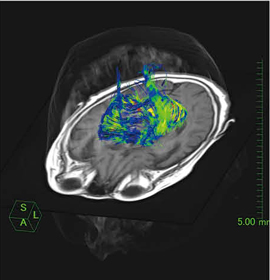

●DTI解析ソフトウェア

認知症は,パーキンソン病から発症するケースがあります。パーキンソン病は,神経変性疾患の1つで錐体路異常を示す疾患ですが,そういった神経線維の情報を可視化して表示できるソフトウェアが,現在開発中の“DTI解析ソフトウェア”です(図2)。

独自の手法により,いままで難しいとされてきた交差した神経線維も明瞭に描出が可能で,脳腫瘍や脳梗塞などの病巣と,神経線維の位置関係把握や術前シミュレーションにも有用です。

図2 DTI解析ソフトウェア(W.I.P.)